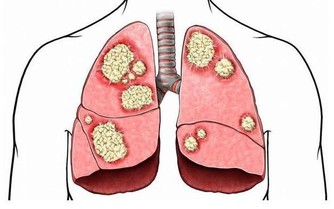

血腥味的屁,很有可能是消化道有出血。血液積聚在患者胃腸道中,胃酸及腸道細菌把血液分解,有時排出的糞便會像柏油一般,屁也會有腥臭味。此外,腸道有惡性腫瘤時,因癌組織糜爛、剝落、出血,再加上細菌的分解發酵作用,放的屁也有腥臭味。

所以,大便顏色成黑色,或是腥臭味的屁,一定要去醫院檢查。